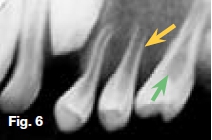

Hypovitaminosis D leads to nondeposition of calcium salt in bone matrix. Figure 5 is a lateral skull radiograph showing generalized radiolucency while figures 6 & 7 are intra-oral and bitewing radiographs of the same patient showing large pulp cavities (green arrow) and attenuation of the lamina dura and dental crypts (yellow arrow). There is also lack of mineralization of the alveolar crest bone (blue arrow). These radiological features are suggestive of Vitamin D-resistant rickets which is an isolated renal tubular defect inhibiting reabsorption of inorganic phosphates, resulting in hypophosphaturia which is inherited as an X-linked dominant trait. The full manifestation of vitamin D-resistant rickets is rickets or osteomalacia non-respondent to vitamin D therapy, as vitamin D metabolism is normal. However, there is diminished intestinal calcium and phosphate absorption. Patients with the milder form may be slightly shorter than normal siblings, with no other manifestation. Females with vitamin D resistant rickets tend to show fewer signs and symptoms than do their brothers.